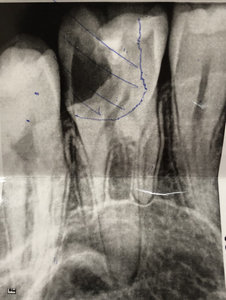

Добрый день. Мне в стоматологии сделали снимок зуба и сказали, что зуб надо удалять, так как вылечить не получится. Подскажите, так ли это? Может стоит обратиться к другим врачам? (фото зуба выслала на e-mail). Зуб № 46. На данный момент зуб не беспокоит. Три месяца назад был флюс, после разреза всё прошло. Антибиотиками не лечила, так как беременность. Сейчас срок 17 недель. Спасибо!

Да, к сожалению зуб необходимо удалить, так как на верхушках всех корней наблюдается обширное воспаление.